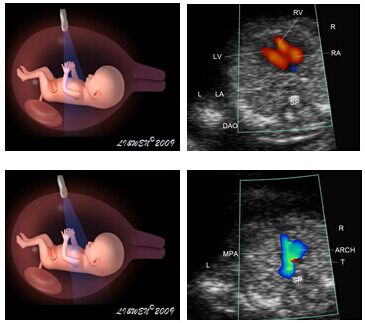

胎儿心脏彩超是能够帮助人们了解胎儿动态心腔内结构、心脏的搏动和血液流动的仪器。

主要检查心脏的形态学有没有什么异常,以及心功能是否正常,特别对先天性心脏病是首选的检查方法。胎儿心脏彩超是对人体没有任何损伤而且能动态显示心腔内结构、心脏的搏动和血液流动的仪器,能够使心脏的各个结构清晰地显示在屏幕上。